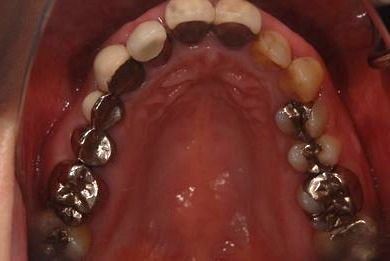

セラミックの症例写真 SHINBI

| 性別/年齢 | 女性 / 41歳 | ||||||||||||||||||||||||||||||||

| 主訴 | 歯が欠けたので、セラミック治療をお願いしたい。 | ||||||||||||||||||||||||||||||||

| 治療方針 | セラミック治療にて、審美的回復を行う。 | ||||||||||||||||||||||||||||||||

| 治療内容 | エンプレスオールセラミッククラウン4本(オールセラミック用土台4本) | ||||||||||||||||||||||||||||||||

| 総治療費 | 408,000円 | ||||||||||||||||||||||||||||||||

| 治療期間 | 4ヶ月 |